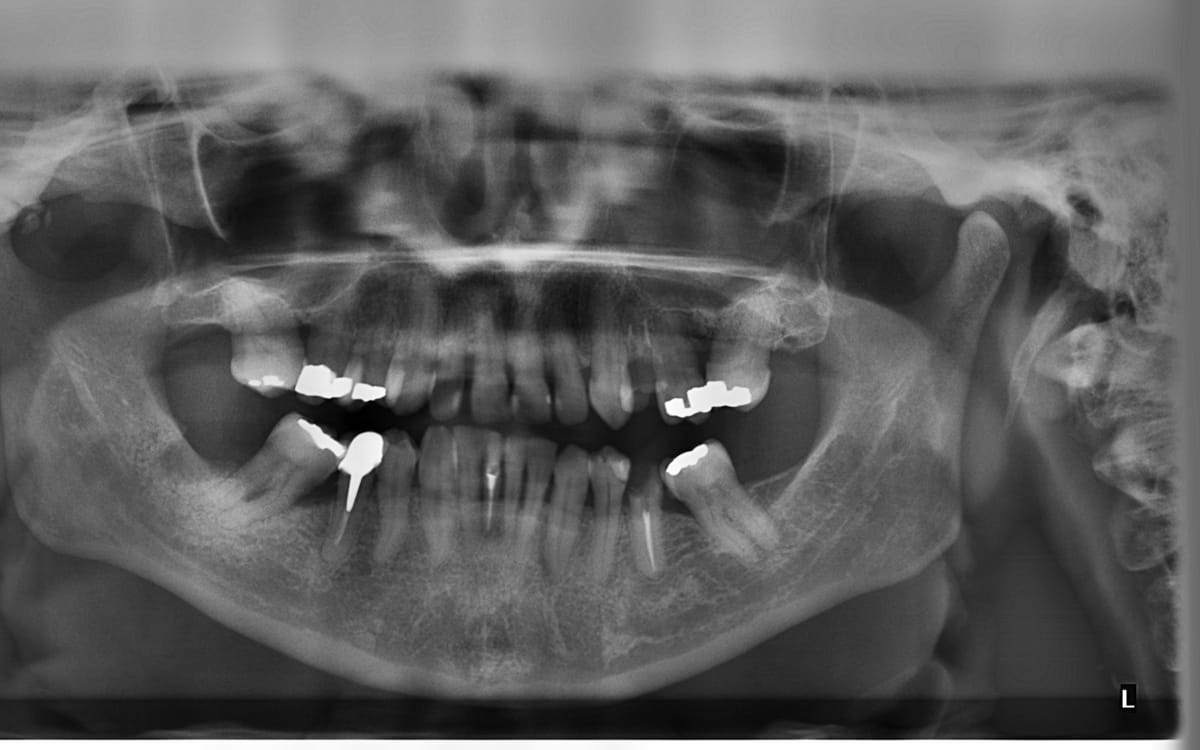

Zo’n anderhalf miljoen mensen in Nederland gaan weleens een jaar niet naar de tandarts omdat ze daar geen geld voor hebben. Jordy is – om financiële redenen – al veel langer niet geweest. En als zijn voortand eruit valt, heeft hij geen flauw idee hoe hij dat moet oplossen.

Het was meteen een openluchtmuseum’, zegt Jordy. ‘Je schaamt je rot. Je kan niet goed kauwen. Je krijgt ontstekingen, die doorwerken door je hele lichaam. En ja, met solliciteren was het rottig. In een winkel werken? Ja, dat kan natuurlijk niet, want het ziet er niet uit.

Als het lachen je vergaat is een korte audiodocumentaire over de gevolgen van ongelijkheid in ons zorgstelsel. Een verhaal over de innige band tussen armoede en kiespijn.

© Jordy